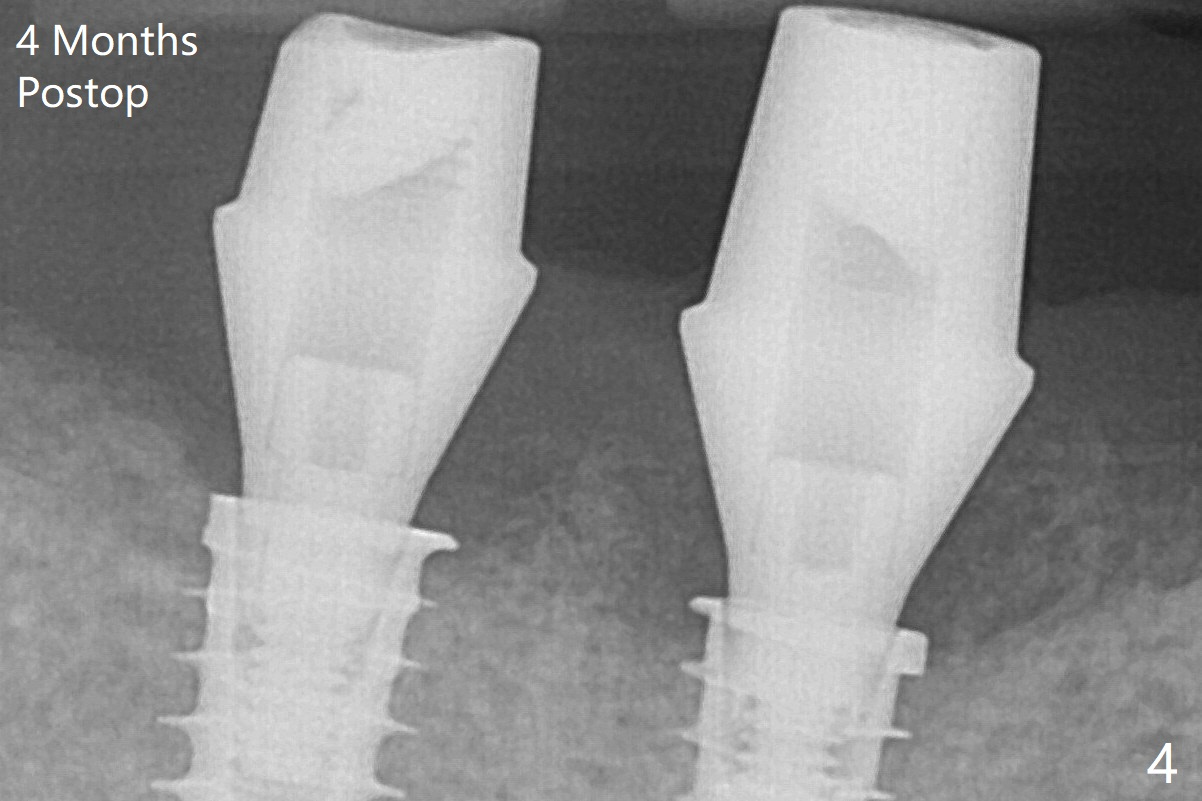

Note bone growth, especially at #30, 2.5 and 4 months postop (Fig.3,4). In fact the abutments are incompletely seated. The crown of #30 is loose with foul smell 2 years 8 months post cementation. It is painful to reinsert the crown/abutment after proximal reduction. A healing abutment is placed (Fig.5). When the incompletely seated abutment at #31 is removed, there is also smell. After separation from the crown, the abutment of #31 returns to the site with change in insertion position, while a smaller abutment has to be used at #30 (Fig.6) due to use of the small healing abutment earlier (Fig.5). A good piece of news is the presence of the bone between the implants (Fig.5,6 *), which contributes to interimplant papilla.